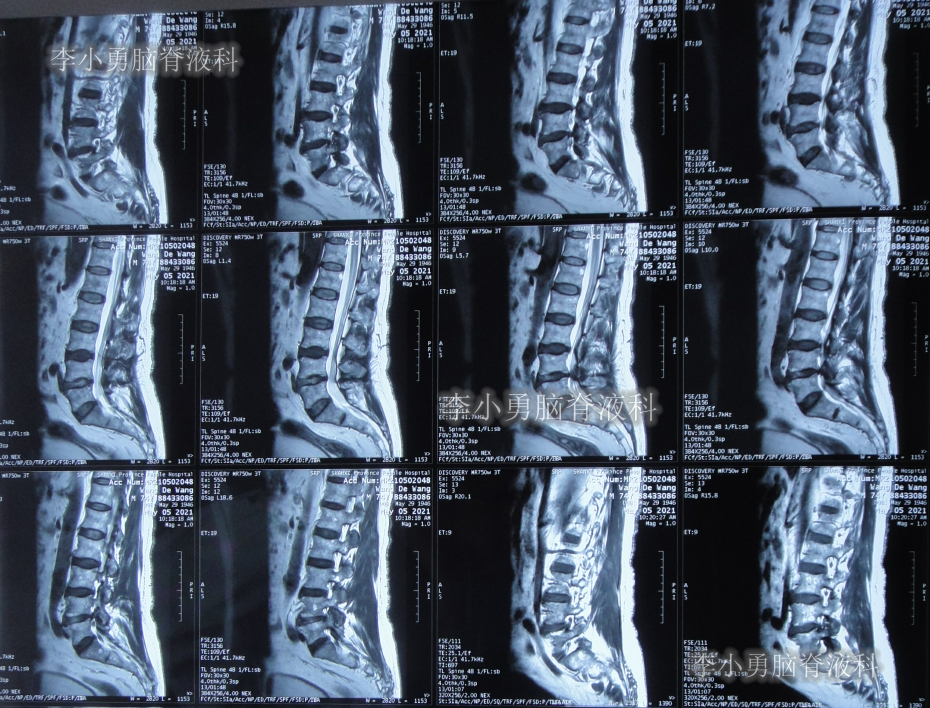

2021年5月5日(腰大池腹腔分流术后38天,即拔除硬膜下血肿引流管16天),查头部核磁和腰椎核磁(图-10、图-11)后认为可能是颅内感染或和堵管。

图-11:2021年5月5日腰椎核磁